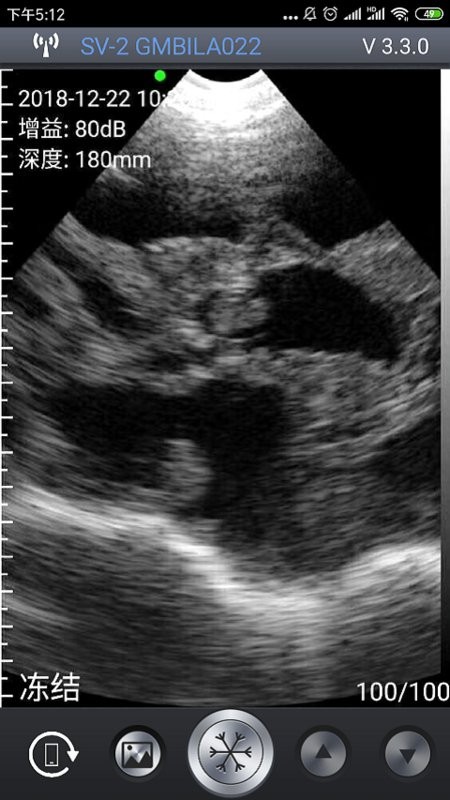

通过最强大的成像功能也是能让你查看到最全面的重要信息内容,任何图片信息都能够以最全面的方式为您介绍;

通过WiFi,以下多种型号的超声探头可以与该软件连接:HD-1,SV-1,SV-2,SS-1,SF-1,SU-2等。在这些不同配置的探头中,总有一款能够满足您的专业需求。